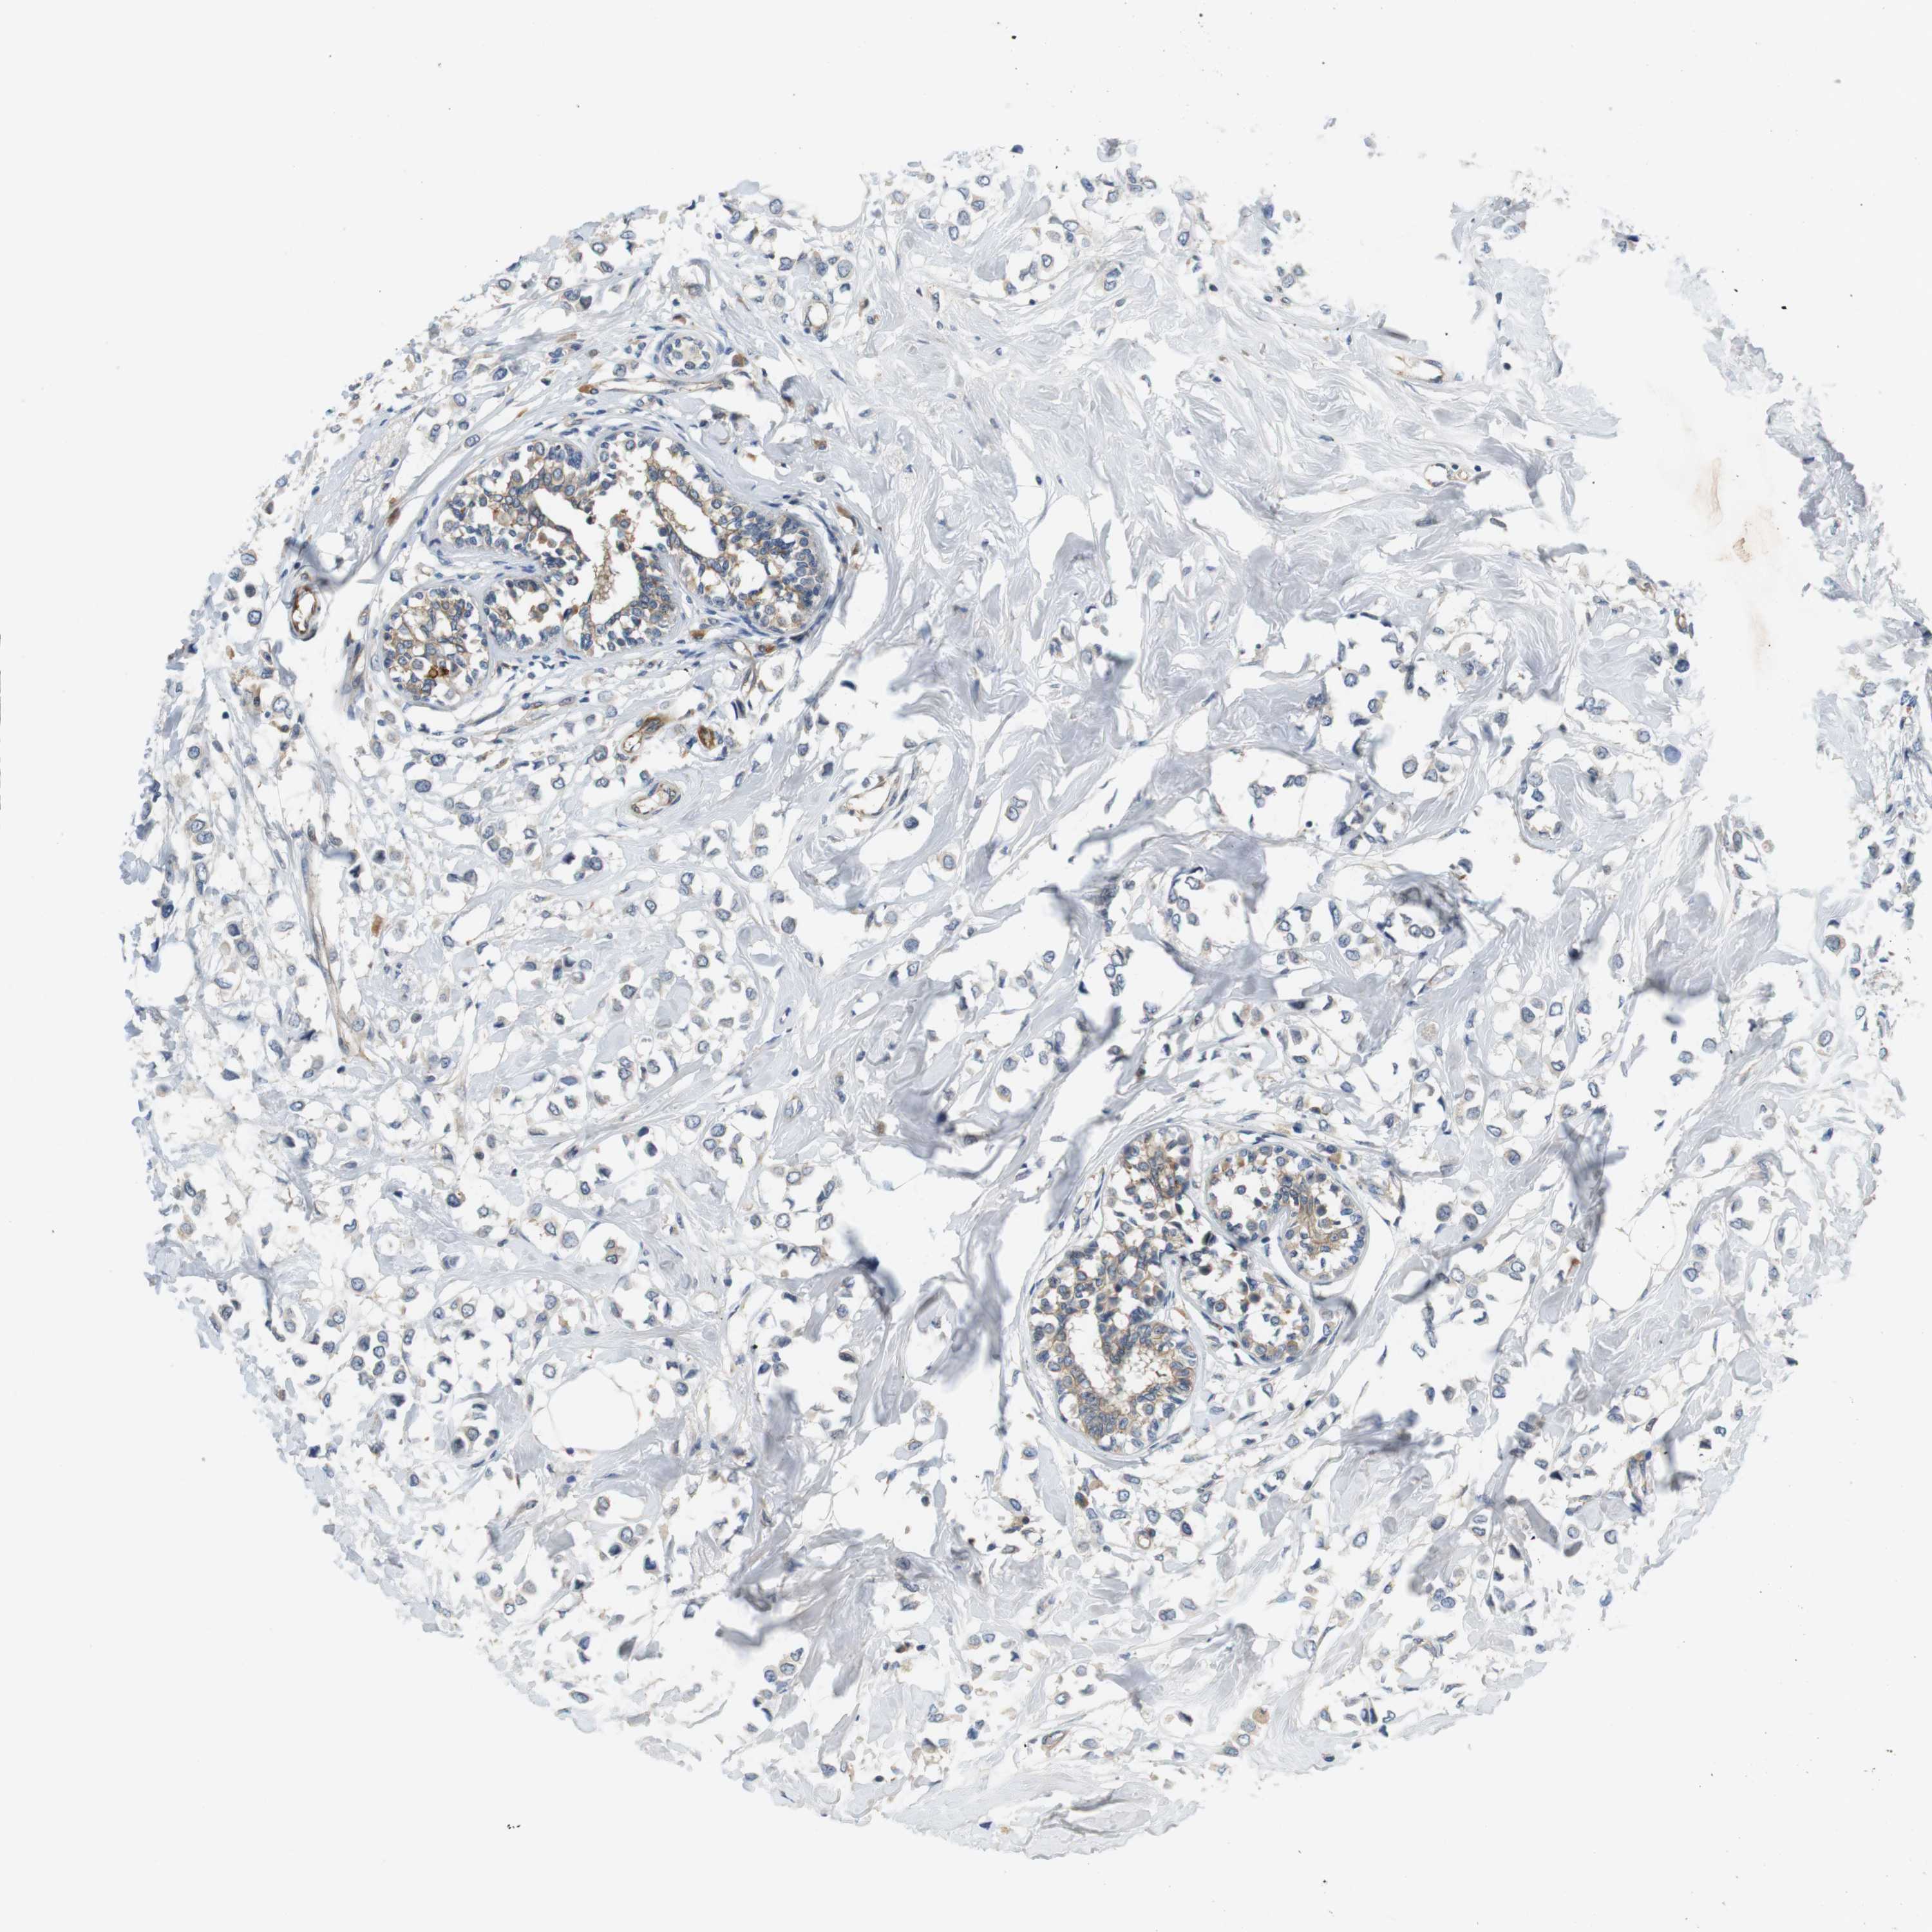

CANCER BREAST CANCER Show tissue menu

BRCA TCGA BRCA VALIDATION PROTEIN EXPRESSION